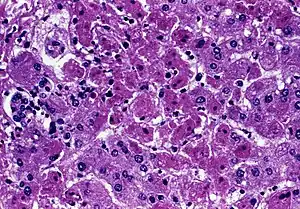

![]() | |

| Transmission electron micrograph of Marburg virus | |